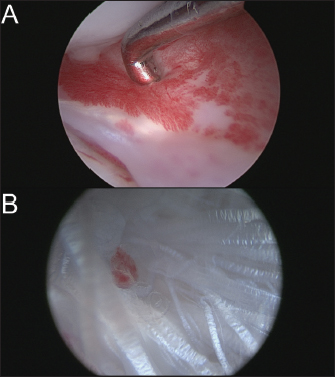

On day 1 post-surgery, the dog was walking on her operated leg with moderate lameness. During each postoperative consultation, two x-rays were performed (face and profile), as well as an orthopedic examination. A LOAD questionnaire was also completed. After 2 weeks, moderate lameness was observed, and radiographs showed thickening of the patellar tendon and moderate synovial inflammation; the LOAD score was 21/52. After 1 month, moderate lameness was persistent, radiographs still showed thickening of the patellar tendon and moderate synovial inflammation; the LOAD score was 13/52. After 2 months, moderate lameness was still observed, radiographs had not evolved, and the LOAD score was 7/52. After 3 months, mild lameness was observed, a mild posterior drawer was reported at orthopedic examination and moderate synovial inflammation was observed on radiographs (Fig. 6); the LOAD score was 7/52. After 6 months, very mild lameness was observed, a mild posterior drawer was reported at orthopedic examination and a resolution of the synovial inflammation was seen on radiographs (Fig. 7); the LOAD score was 5/52. After a year, a persistent yet stable mild posterior drawer was reported at the orthopedic examination but was not associated with any lameness, and the LOAD score was down to 2/52.

Fig. 6. 3-month postoperative radiographic views of dog's right pelvic limb from side (left) and front (right).